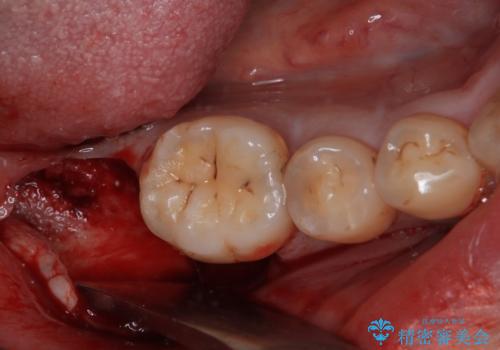

部分矯正で咬み合わせを改善 奥歯のインプラント治療

- 左下欠損部のインプラント治療を希望して来院された患者様です。

左下の欠損部を長期間欠損を放置していたことで、咬み合う上の奥歯が動いてしまっていたので、まずは上顎奥歯の部分矯正を行うこととしました。

理想的な咬み合わせに改善した上で、インプラント補綴治療を行うこととしました。

部分矯正を行ったこと治療期間は長くなりましたが、違和感のない咬み合わせを達成することができました。